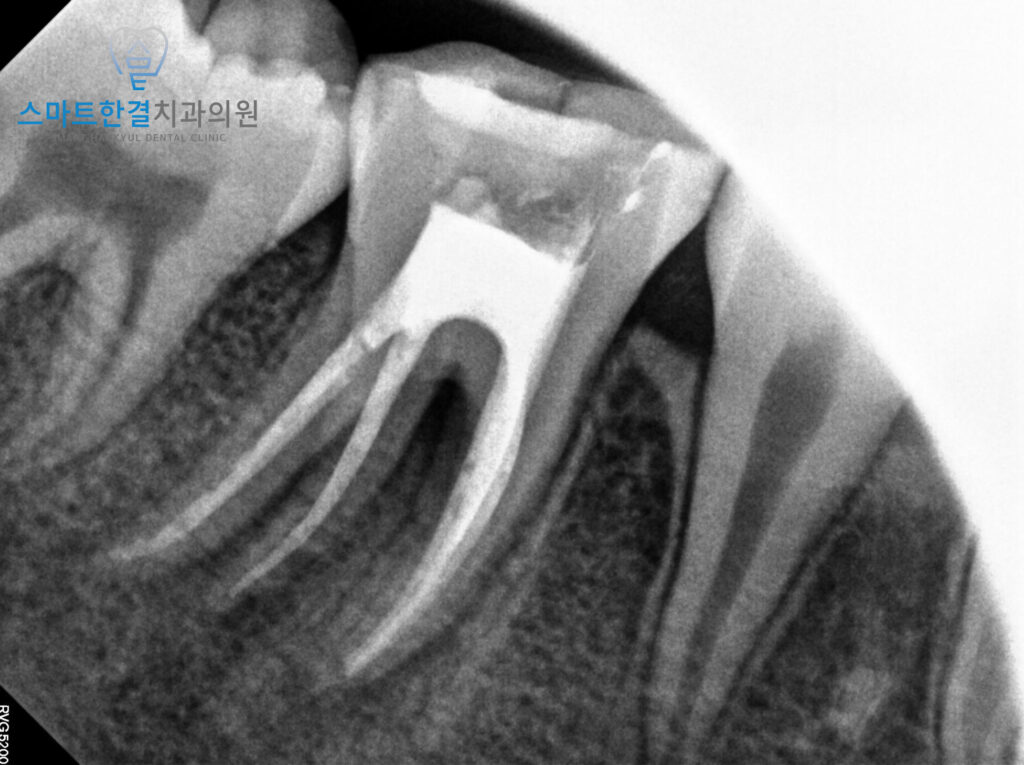

앞서 설명드렸던,

뿌리가 성장이 되어있지 않았을 가능성을

염두에 두고 치료를 진행하였는데요.

확인해 보니,

뿌리 끝 폐쇄가 이루어져 있어

통상적인 신경치료를 진행하여

마무리할 수 있었어요.

신경치료 시에는

감염된 부위를 철저히 소독하고,

신경을 제거한 후 빈 공간을 깨끗하게 청소하여

감염이 다시 발생하지 않도록 하였으며

치료가 끝난 후 치아 내부를 밀봉하여

추가적인 문제를 예방할 수 있도록 했어요.

26.02.12

이렇게 신경치료가 끝난 후,

6개월 뒤 정기검진 차 내원하셨을 때

염증의 재발 없이 치아가 깨끗하게

회복된 것을 확인할 수 있었어요.

치료 후 상태가 안정적으로 유지되어,

치아와 잇몸 건강이 잘 회복된 모습을 보였답니다.^^